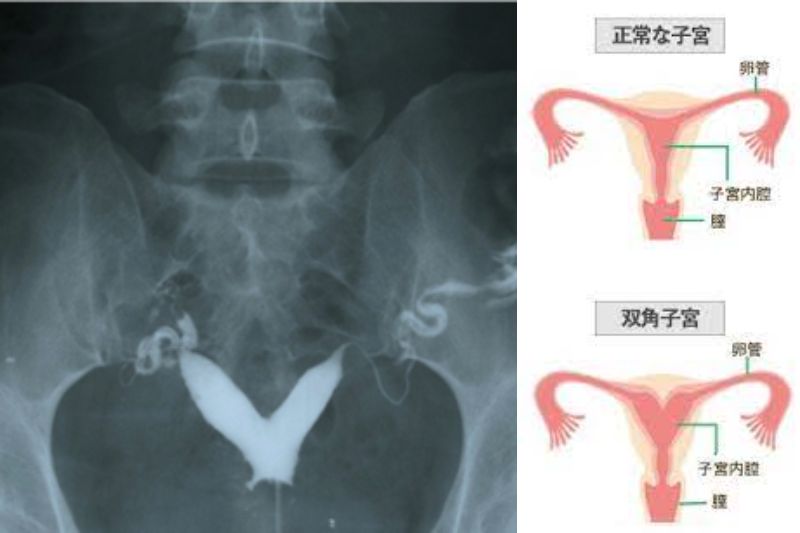

当院の病院を受診された患者様は、一人目を妊娠して21週目頃に子宮の異常がわかり、死産となりました。このことで、子宮鏡で双角子宮の手術を行いました。これらの原因が見つかっても、必ず流産するわけではありません。

まずは、採血にて 先天性血栓形成素因(血液凝固機能異常)、抗リン脂質抗体、内分泌検査、夫婦染色体検査などの検査をおこないます。また、子宮の形態について調べるには、子宮卵管造影検査、超音波(エコー)検査、子宮鏡検査、MRI検査などがあります。何度も流産した場合は、流産した赤ちゃんの絨毛という部分(妊娠早期の胎盤の一部)の組織を採取し、染色体異常の有無を調べます。